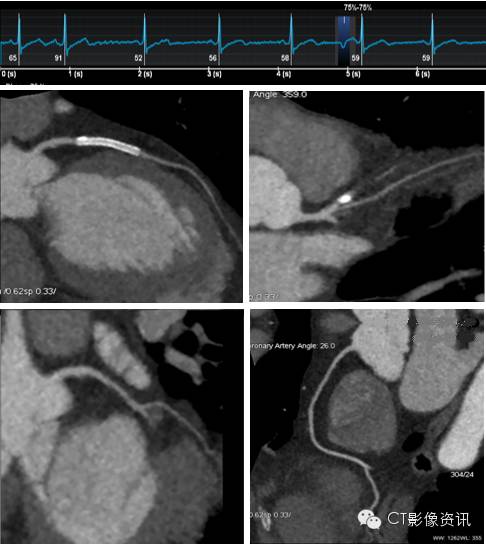

Case 4 男性,63岁,支架术后复查。

扫描协议 探测器宽度:120mm, Axial; 管电压和管电流:70kV, Smart mA; 旋转速度:0.28s/rot ;迭代:ASiR-V 50%;体重指数:23.4; 对比剂:270mgI/ml, 25ml, 4.2ml/s; 扫描剂量:0.166mSv。

点评 冠脉支架植入是治疗冠心病冠脉狭窄的主要方法之一。Revolution CT 使用了宝石探测器、视网膜集成化数据采集系统,全新的HD 高清扫描模式,实现了0.23mm的可视空间分辨率, 最新的ASiR-V 迭代重建平台,能较好的显示支架腔内的情况,并对整个冠脉及支架做出精确评估。